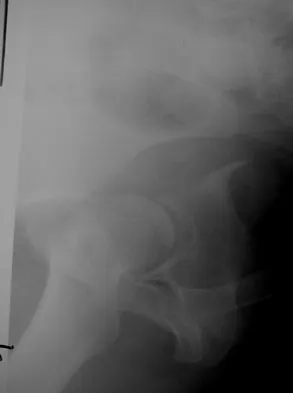

Which of the following choices best describes the fracture pattern shown in Figures 2a through 2c?

Explanation

The fracture pattern shown in the radiographs is a fracture of the posterior column. The only line interrupted on the AP pelvis is the ilioischial line. The obturator oblique view shows that the iliopectineal line is intact as is the outline of the posterior wall. The iliac oblique view shows an interruption of the ilioischial line and an intact anterior wall. Therefore, this fracture is a fracture of the posterior column. Letournel E, Judet R: Fractures of the Acetabulum, ed 2. Berlin, Germany, Springer Verlag, 1993.